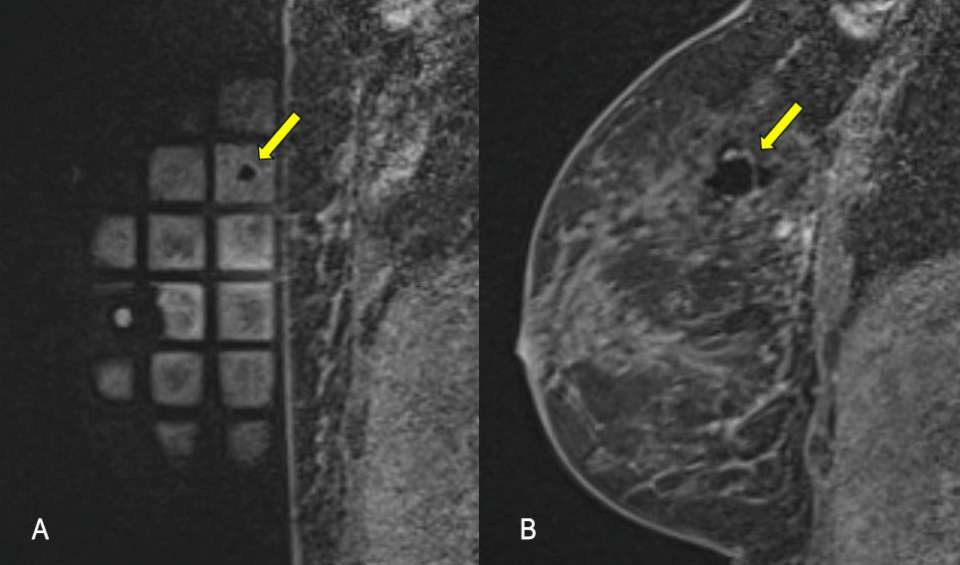

Procedure MRI Guided Breast biopsy Figure 4

Figure 4. Post-biopsy craniocaudal mammogram confirms post-biopsy micro-clip placement.

• Perform a post-procedure mammogram to demonstrate accurate placement of the micro-clip (fig 4)